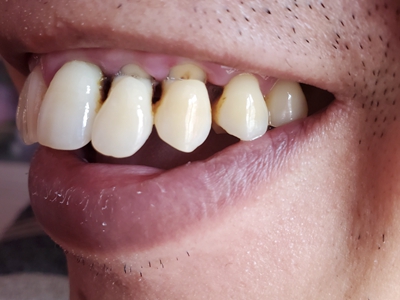

楔状缺损症状图片

楔状缺损是一种非龋性牙颈部慢性损伤,是指发生在牙齿唇、颊面颈部的慢性硬组织缺损。典型缺损由两个夹面组成,口大底小,呈楔形。楔状缺损多发生于中老年人,主要原因是刷牙不当,防治措施是调整咬合关系,改善刷牙方法,配合相应的治疗。

楔状缺损与年龄相关,即年龄越大,缺损越重,患者多有横刷牙习惯,患牙为多颗甚至全口,常以口角附近的牙齿(尖牙、前磨牙)为重。典型表现为牙颈部缺损,呈楔形,由两个夹面组成,口大底小,缺损处质地坚硬,表面光滑,边缘整齐,无染色,轻微泛黄常为牙齿本色,严重时可导致牙髓腔暴露甚至牙齿横向折断,根据缺损深浅不同,可伴有牙齿敏感甚至疼痛。